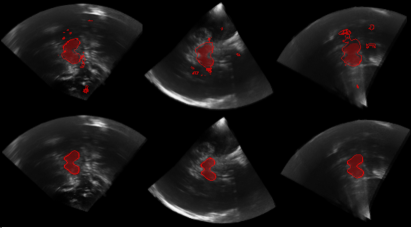

Transcranial ultrasound (TCUS) can be used to scan deep brain regions non-invasively through the temporal bone window. Using TCUS, hyper-echogenicities of the Substantia Nigra (SN) can be analysed, gaining valuable information to perform differential [11] and early [12] diagnosis of Parkinson’s Disease (PD). A crucial step towards computer assisted diagnosis of PD is midbrain segmentation [13, 14]. This task is reportedly challenging even for human observers [15]. In order to penetrate the skull, low frequencies need to be applied resulting in an overall reduction of the resolution and in the presence of large incoherent speckle patterns. Scanning through the bone, moreover, attenuates a large part of the ultrasound energy, leading to overall reduction of the signal-to-noise ratio, as well as low contrast and largely missing contours at anatomic boundaries. Additionally, the higher speed of sound in the bone leads to phase aberration [16] and de-focussing of the ultrasound beam which causes further lowering of the image quality. A variety of image TCUS quality, anatomical visibility and 3D ultrasound fan geometry can be seen in Figure 3. Registration methods, in particular non-linear registration, are very difficult under these conditions. Therefore, atlas-building and atlas-based segmentation methods tend to fail in ultrasound.

Visual examples of ultrasound segmentation results are visible in Figure 3. It is notable that the Hough-CNN segmentation is able to localise and segment the midbrain accurately, regardless of whether the scan was acquired through the left or right bone window. It is also robust to bone window quality and overall visibility of structures, as well as signal-drop regions and blurring.